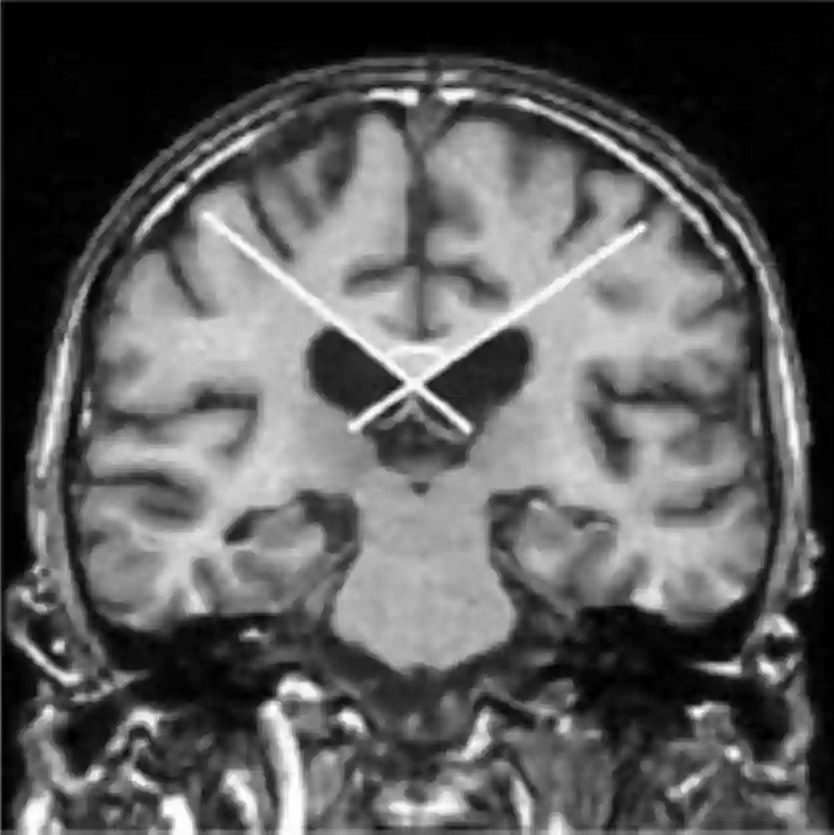

Eine korrekte Messung des Corpus callosum Winkel wird in einer echten koronaren Schicht durchgeführt, welche an der Commissura posterior zentriert ist und orthogonal zur AC-PC Linie und Fissura longitudinalis cerebri ausgerichtet ist. Auf dieser Schichtebene wird dann der Winkel zwischen der medialen Wand des Seitenventrikels gemessen[^2].

Corpus callosum Winkel MRI

Berechnung des Corpus callosum Winkels im coronaren MRI Bild. Abbildung adaptiert aus Ishii K. et al.